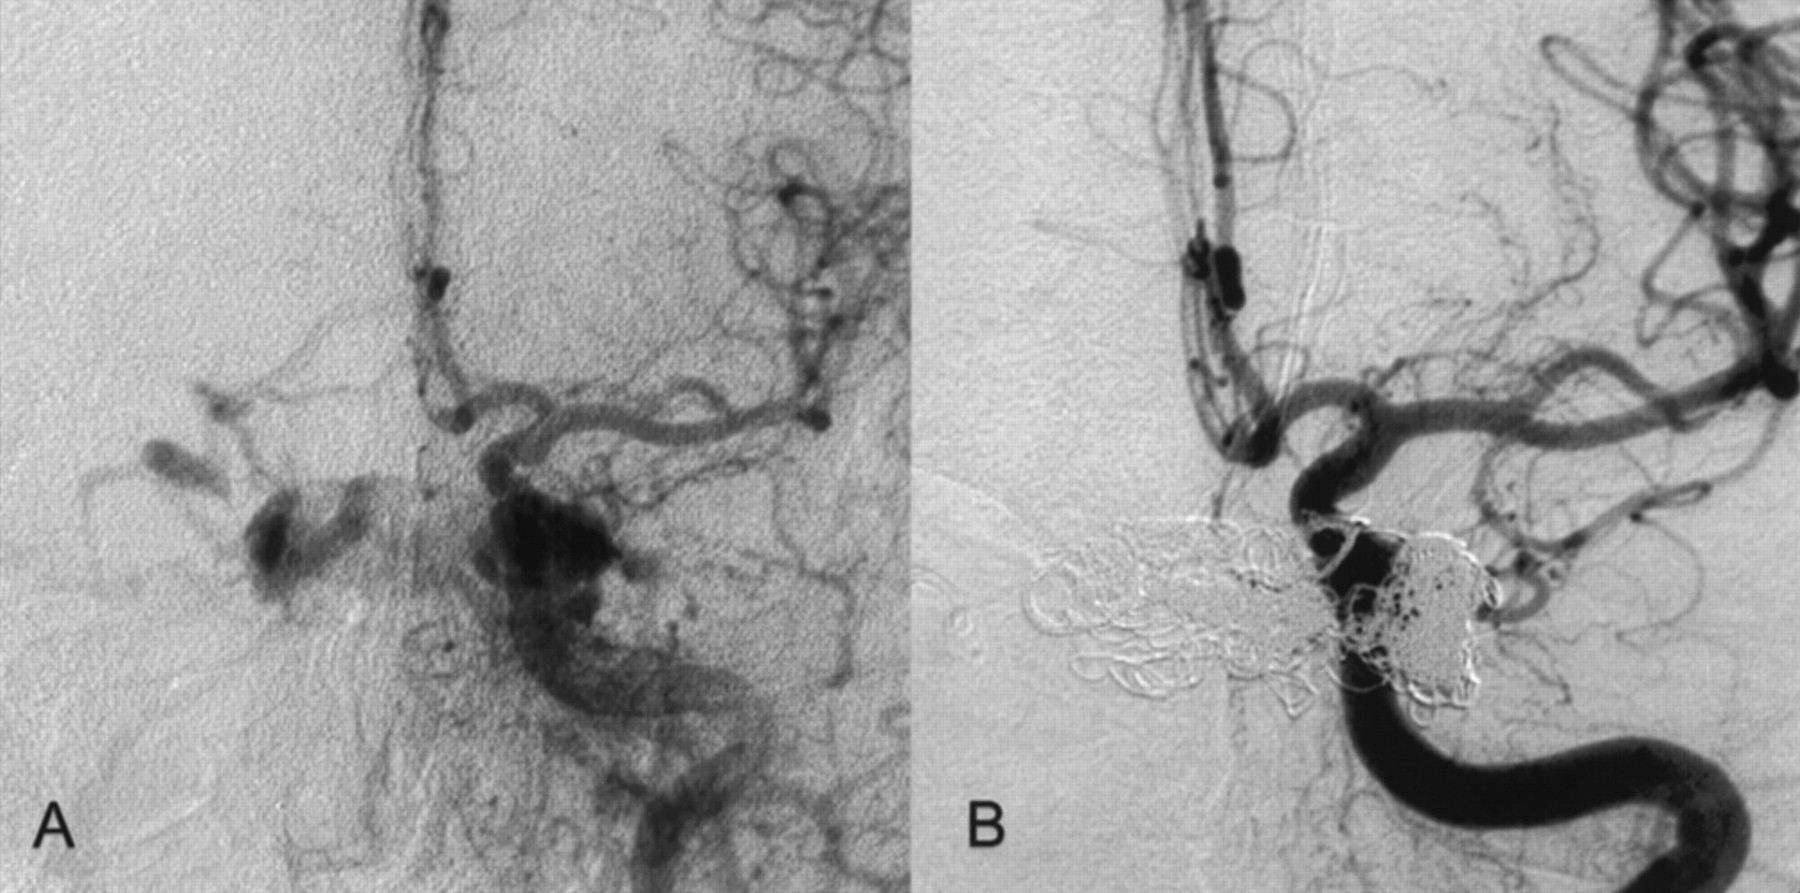

Right CCA.

A, Before treatment.

B, After successful CCF treatment.

Two months before admission, a 74-year-old woman developed diplopia, exophthalmus on the left side, scotomas, left visual blur, and left conjunctival injection. MR imaging, MR angiography, CT, and duplex sonography revealed a CCF. At the time of admission, the patient had exophthalmus on the left, visual disturbance, diplopia, bilateral abducens nerve palsy, and left oculomotor nerve palsy. Angiography revealed a Barrow type D CCF with bilateral fistulae of the cavernous sinus fed by multiple meningeal branches of the external carotid artery on both sides, by the anterior meningeal branch of the left vertebral artery, and by the internal carotid artery on the left side (Figs 1 and 2). The CCF drained from the cavernous sinus into the right SOV, the left pterygoid venous plexus, the left inferior petrosal sinus, and via cortical veins into the straight sinus and the lateral sinuses on both sides. The right inferior petrosal sinus could not be detected. In contrast to the initial MR angiography performed 4 weeks earlier, the angiography showed the left SOV being thrombosed.

However, the CCF could not be occluded despite the deployment of another nine GDCs. Therefore, a second microsurgical approach via the thrombosed left SOV was attempted. The surgical procedure was performed as on the contralateral side; however, the thrombosed SOV was not easy to detect and prepare. Intraoperative micro-Doppler imaging confirmed the thrombosis of the left SOV. The vein was punctured nevertheless, and under fluoroscopy, a microguidewire could be pushed forward through the soft thrombus. This allowed intracavernous placement of a two-tip Tracker 18, with successful endovascular occlusion of the CCF being achieved after an additional deployment of eight GDCs (Figs 1 and 2).